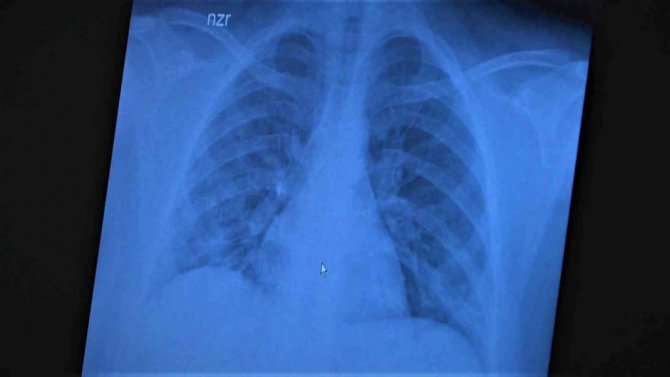

Korona virüsün mutasyona uğramış hali artık aşısız çocuklara ciddi zararlar vermeye başladığına dikkat çeken Göğüs Hastalıkları Uzm. Prof. Dr. Özkaya, 11 ve 14 yaşlarındaki koronaya yakalanmış ve ciddi akciğer tutulumlarıyla tedavi gören çocukların akciğer tomografilerini gözler önüne serdi.

Çocukların akciğer tomografilerini inceleyen Özkaya, "11 yaşında kovid pozitif bir öğrencimiz, yüksek ateş ve nefes darlığı ile bize geldi. Ciddi akciğer tutulumu var. Geçen yıl "bu çocuklar hastalıktan etkilenmiyor" diyorduk. Bu çocukta görüyorsunuz buzlu camlar ve konsolidasyon alanlarla seyrediyor. Geçen yıl bu şekilde çok çocuk görmüyorduk. Önümüzdeki aylarda bu şekilde devam ederse çocuklarımızı kaybetmeye bile başlayabiliriz. 14 yaşında pozitif olan bir diğer çocuğumuz ise aşı randevusu almış ama aşısını olmadan ateş ve öksürükle başvurdu. Halen şanslıyız. Çocuklar çok hızlı tedaviye yanıt veriyor. Düzeldi. Çekilen tomografisinde ise bilaterel yaygın tutulumları vardı. Bu ise 24 yaşında genç hastanın akciğer tomografisi. Bu kişide yaygın akciğer tutulumları görüldü. Bunu da tedavi ettik. Önümüzdeki aylarda ne getirecek ne götürecek beraber göreceğiz. Özellikle havaların soğumasıyla kapalı ortamlarda geçilen zamanın ve kalabalıkların etkisiyle vaka sayılarının önümüzdeki günlerde artacağını biliyoruz. Şu an gerçekten hastalık gençlerde 30 -40 yaş altı gençlerde görülmeye başladı. Poliklinik şartlarında olanların büyük bir kısmı 30 yaş altı hastalar. Servislerde yatanlarda orta yaş ve altı nüfus. Yoğun bakımda yatanların büyük bir kısmı ise aşısız erişkin insanlardan oluşuyor" diye konuştu.